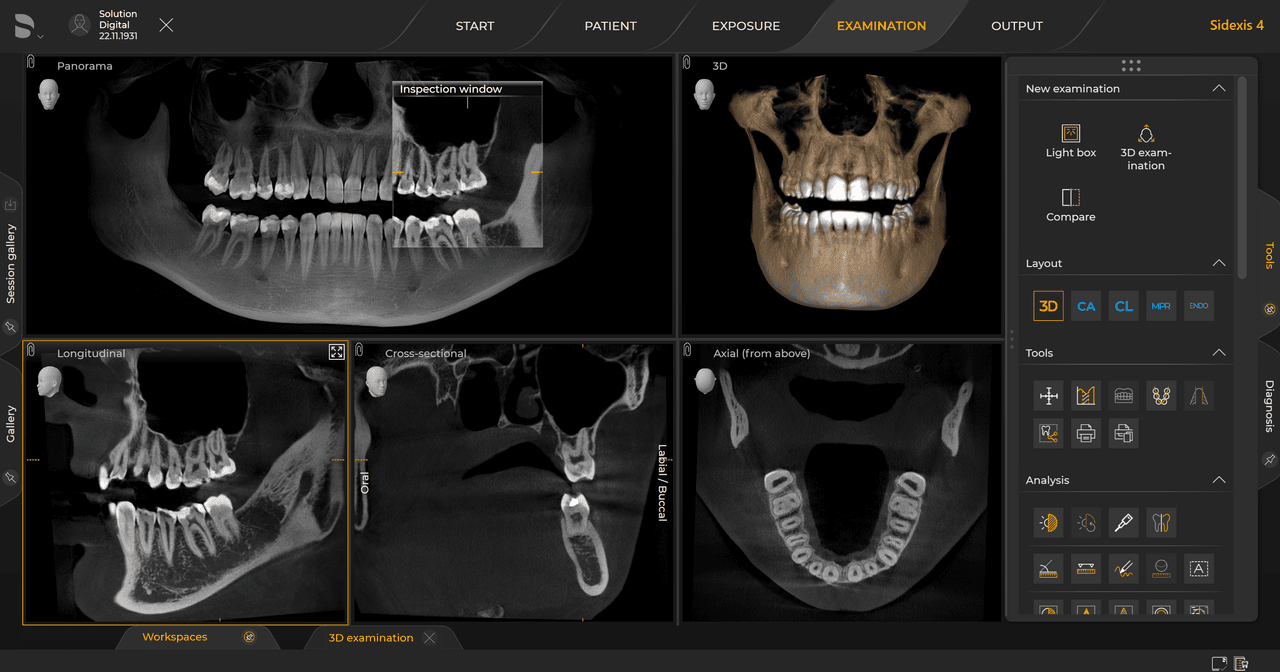

Dentsply Sirona Röntgengeräte arbeiten exklusiv mit Sidexis 4. Aber die Datenmigration von Sidexis XG zu Sidexis 4 ist sehr einfach. Wir empfehlen den Wechsel zu Sidexis 4, um die vollen Vorteile des digitalen Prozesses mit den neuesten Werkzeugen zu erleben.